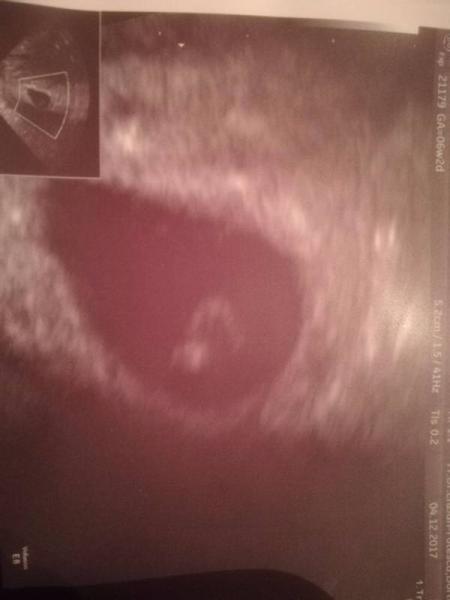

Jep, sieht bei mir so ähnlich aus war heute auch beim FA bei 6+1 oder 6+2..War auch der Dottersack mit 3 mm Embryo und ganz zaghafter Herzschlag..Also wird alles ok sein bei Dir..hänge mal mein Bild von heute mit dran..lg

Ja, mein Bild ist ran gezoomt deshalb sieht das so aus..live sah es aus wie bei dir..Ist total normal ist der Dottersack der soll so aussehen